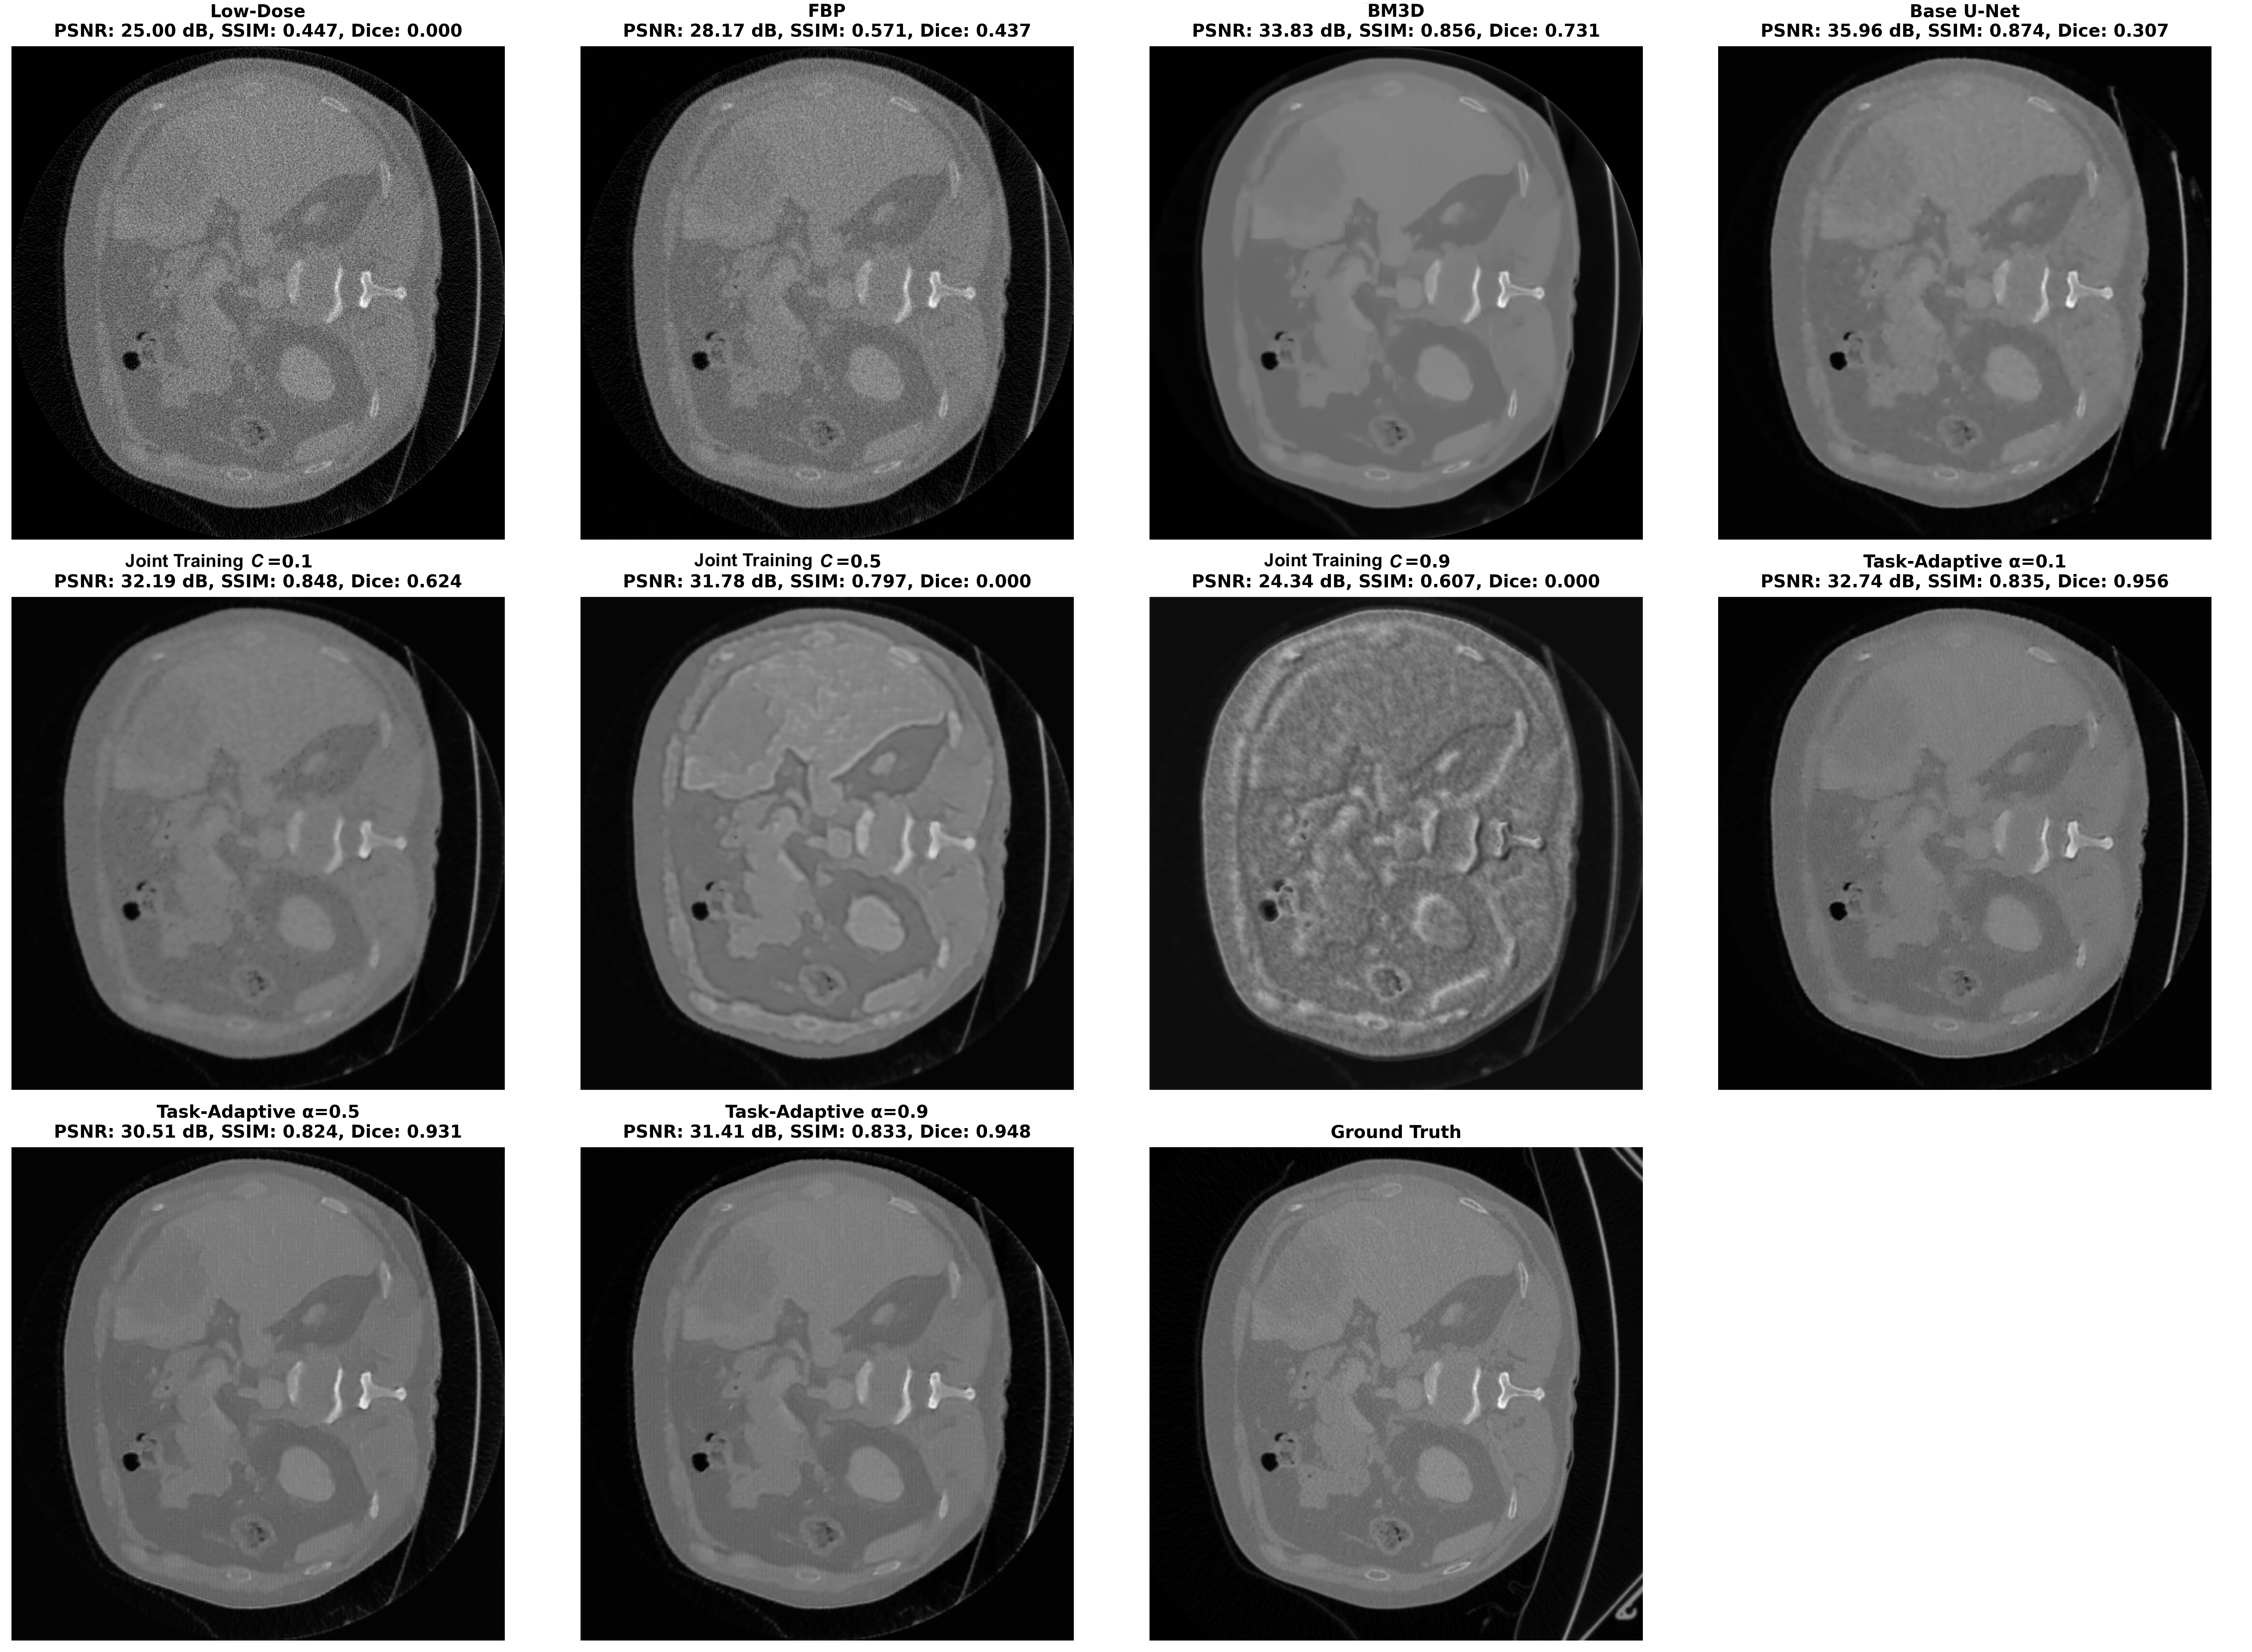

Fig. 3 shows the reconstruction visuals alongside low-dose scan and ground truth full-dose scan. It can be observed that FBP improves from the low-dose scan in a very small sense, which can only be seen with a detailed inspection. Base U-Net’s reconstruction preserves the pixel intensities of ground truth better than FBP, but the background is still grainy and artifacts remain. However, it is still an improvement from the low-dose scan. Joint training with equal to 0.1 provides similar results to Base U-Net in this sense. Joint training approaches with equal to 0.5 and 0.9 diverge from satisfactory reconstructions both losing significant diagnostic details, especially the one with 0.9. BM3D provides an important reconstruction that has sharp edges with clear details, yet image is oversmoothed when compared with the ground truth scan. Still, it contains the details better than every other method, except our task-adaptive models. All three instances of the task-adaptive models provide great reconstructions for this sample. However, models with equal to 0.5 and 0.9 provide the best results, with the reconstructions being very close to ground truth full-dose scan.

Fig. 4 shows the predicted segmentation maps of pre-trained segmentation model for the sample in Fig. 3, from low-dose scan, its corresponding reconstructions and ground truth full dose scan, alongside with the ground truth segmentation map as reference. It is clearly seen that segmentation model failed to conduct any segmentation from the low-dose scan and joint training approaches with equal to 0.5 and 0.9. It also provided a very poor segmentation for FBP, covering just a part of the liver which is shown in green and only a covering a very small part of the tumor which is shown in red. The segmentation of the Base U-Net reconstruction covers a larger portion of the total area, but misclassifies the liver as tumor, and fails to segment the true tumor. Similarly, the reconstruction from the joint training approach with equal to 0.1 leads to a segmentation that captures the overall area well, but contains significant misclassifications between the liver and tumor. The BM3D reconstruction enables an highly accurate segmentation of the liver, yet it still fails to detect a big part of the tumor. Unlike other methods, all of our task-adaptive models produce reconstructions that yield very good segmentation results, that align well with the segmentation of the full-dose scan. In particular, our models with equal to 0.5 and 0.9 yield reconstructions that produce segmentation maps, nearly indistinguishable from the ground truth.